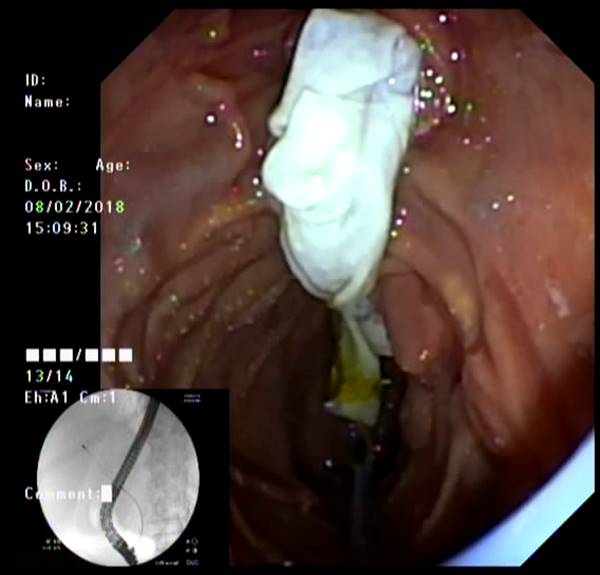

Представлены клинические наблюдения редкого осложнения эхинококкоза печени – прорыва эхинококковой кисты в желчные протоки. Осложнение стало причиной обструкции желчных протоков, механической желтухи и холангита. Освещены этапы диагностики, роль УЗИ в выявлении осложнений эхинококкоза печени, рассмотрены способы минимально инвазивного лечения с применением эндоскопических и чрескожных технологий под контролем лучевых методов.